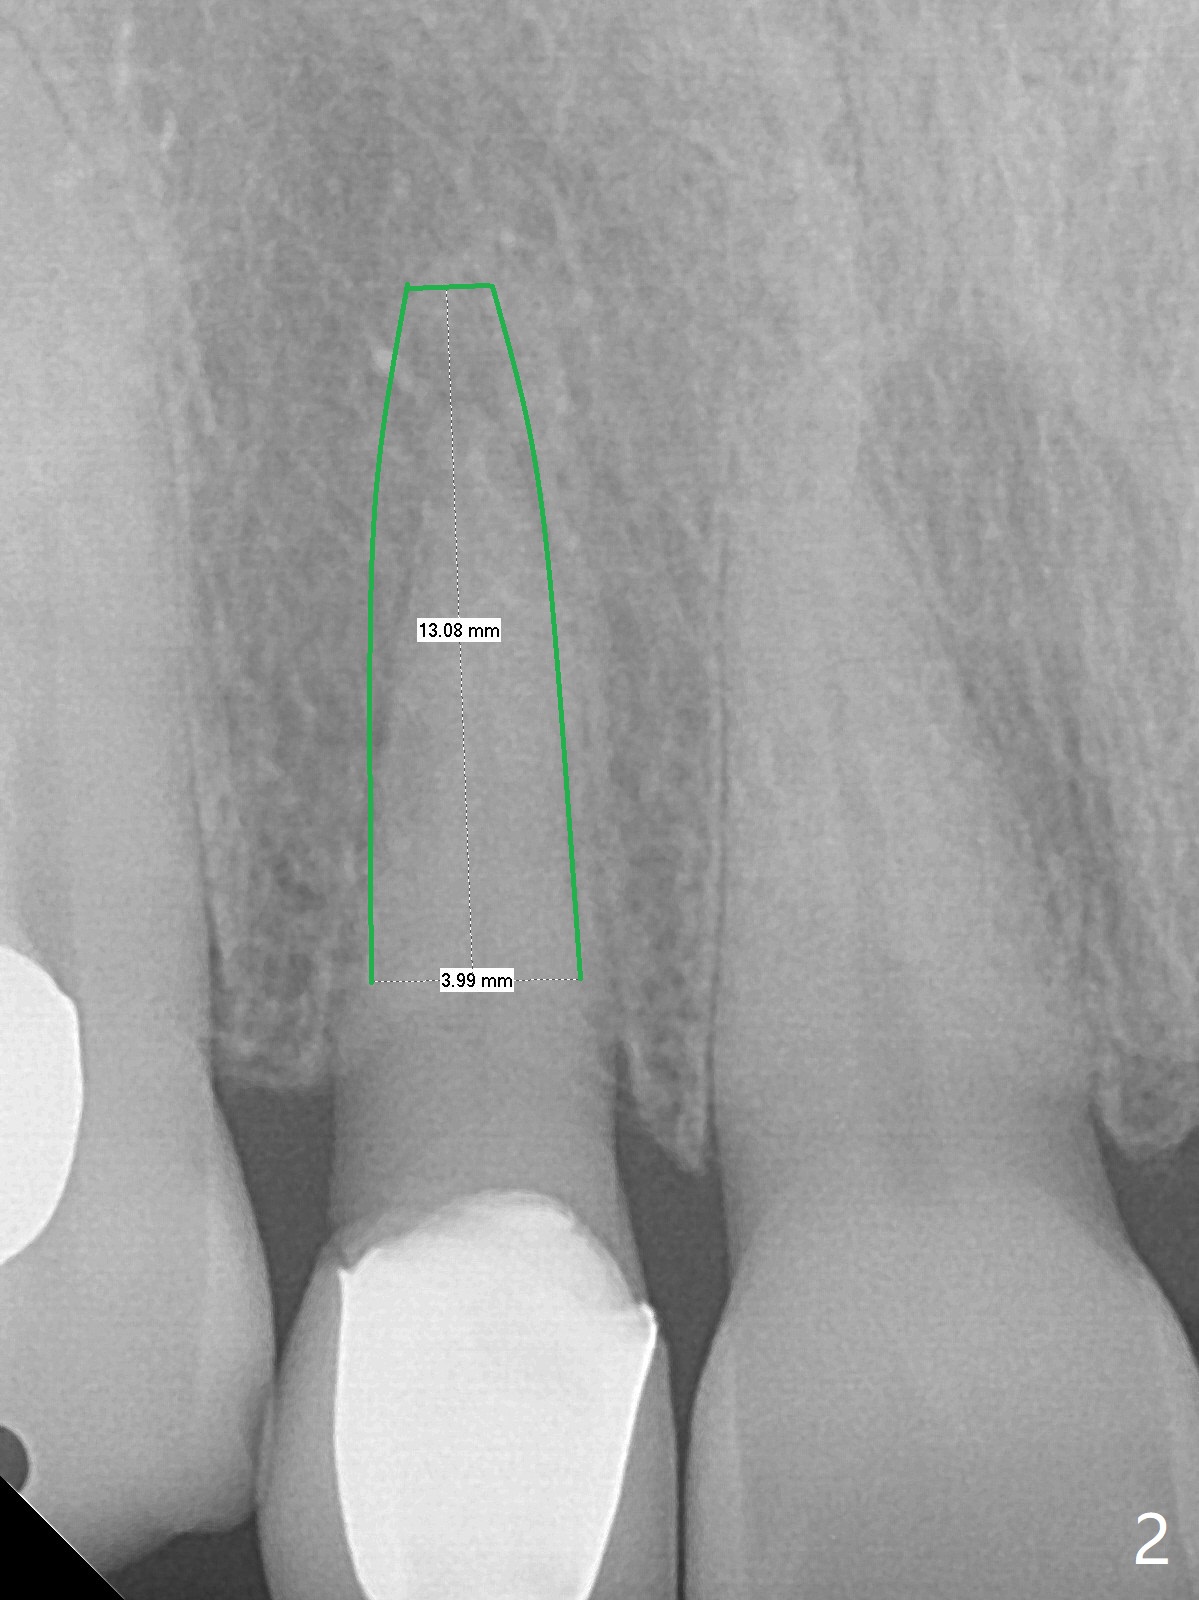

A 63-year-old woman has felt the tooth #7 with a crown and PARL loose for the last 4 months (Fig.1 >).  The crown finally fractures equigingival.  It appears that the best option is extraction and implant (Fig.2).  A 13 mm long implant seems to be short.  A 15 or 16 mm long bone-level or 17 or 20 mm tissue-level one is more appropriate.  To prevent buccal crest and plate loss, socket shield will be performed.  Since the tooth is necrotic, make sure to remove the pulp.